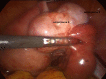

Figure 4

Image coelioscopique montrant l'hématosalpinx droit avec les 2 corps jaunes